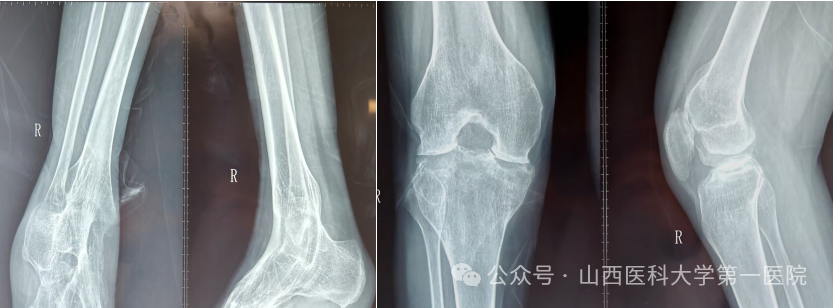

一名42岁的强直性脊柱炎患者,多年来饱受病痛折磨。随着病情进展,双侧髋关节逐渐“锈死”,无法弯腰、下蹲,甚至连坐下都成了奢望——吃饭只能站着,休息只能躺着,生活自理能力几乎丧失。接诊后,骨科杨自权主任团队对患者进行全面检查,发现患者不仅脊柱强直呈“板状腰”,双侧髋关节出现严重融合,而且双膝、双踝关节功能明显下降,手术难度极大。

强直性脊柱炎伴髋关节病变的置换手术,被誉为骨科领域的“硬仗”。杨自权总结此类患者三大诊疗难点:一是麻醉困难,患者脊柱强直,常无法配合常规麻醉体位;二是解剖变异,长期炎症导致关节周围骨质疏松、肌肉萎缩,手术视野不清,风险极高;三是对手术精度要求更高,假体安放的位置、角度稍有偏差,就会影响术后关节稳定性及使用寿命。